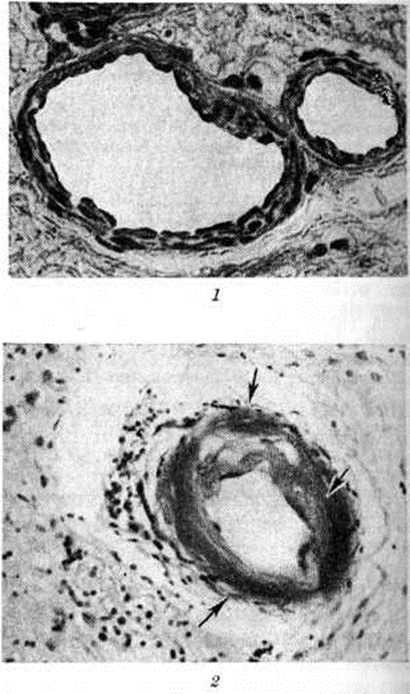

Геморрагический инсульт, как правило, возникает при заболеваниях, протекающих с повышенным артериальное давление. Это обусловлено тем, что сосудистые кризы (смотри полный свод знаний), характерные для гипертонической болезни (смотри полный свод знаний) и артериальной гипертензии (смотри полный свод знаний Гипертензия артериальная), приводят к морфологический изменениям стенок внутримозговых сосудов с нарушением их проницаемости — плазматическому пропитыванию (рисунок 1), некрозам (рисунок 2), образованию микроаневризм (рисунок 3) и их разрывам. Разрыв врождённых артериальных и артериовенозных аневризм может протекать на фоне нормального давления. Преимущественная локализация и характер геморрагий определяются особенностями ангиоархитектоники различных отделов мозга. При гипертонической болезни наиболее тяжёлым изменениям подвергаются сосуды подкорковых узлов и зрительного бугра. Это объясняется отхождением глубоких ветвей под прямым углом от средней мозговой артерии, являющейся продолжением внутренней сонной артерии, и незначительным числом анастомозов сосудов в этой области. В связи с этим на вскрытии кровоизлияния наиболее часто (40%) обнаруживаются в подкорковых узлах с распространением в прилежащее белое вещество (так называемый латеральные кровоизлияния, то есть расположенные латерально от внутренней капсулы, рисунок 4). Второе место по частоте (16%) занимают обширные кровоизлияния, разрушающие подкорковые узлы, внутреннюю капсулу, зрительный бугор (так называемый смешанные кровоизлияния — рисунок 5). Кровоизлияния в зрительный бугор (так называемый медиальные — рисунок 6) составляют 10%, в мозжечок — 6—10%, в мост мозга — 5% от общего числа внутримозговых геморрагий. Кровоизлияния только в белое вещество полушарий мозга встречаются крайне редко. Подразделение полушарных кровоизлияний на латеральные, медиальные и смешанные имеет особое значение в связи с хирургическим лечением геморрагического Инсульт.